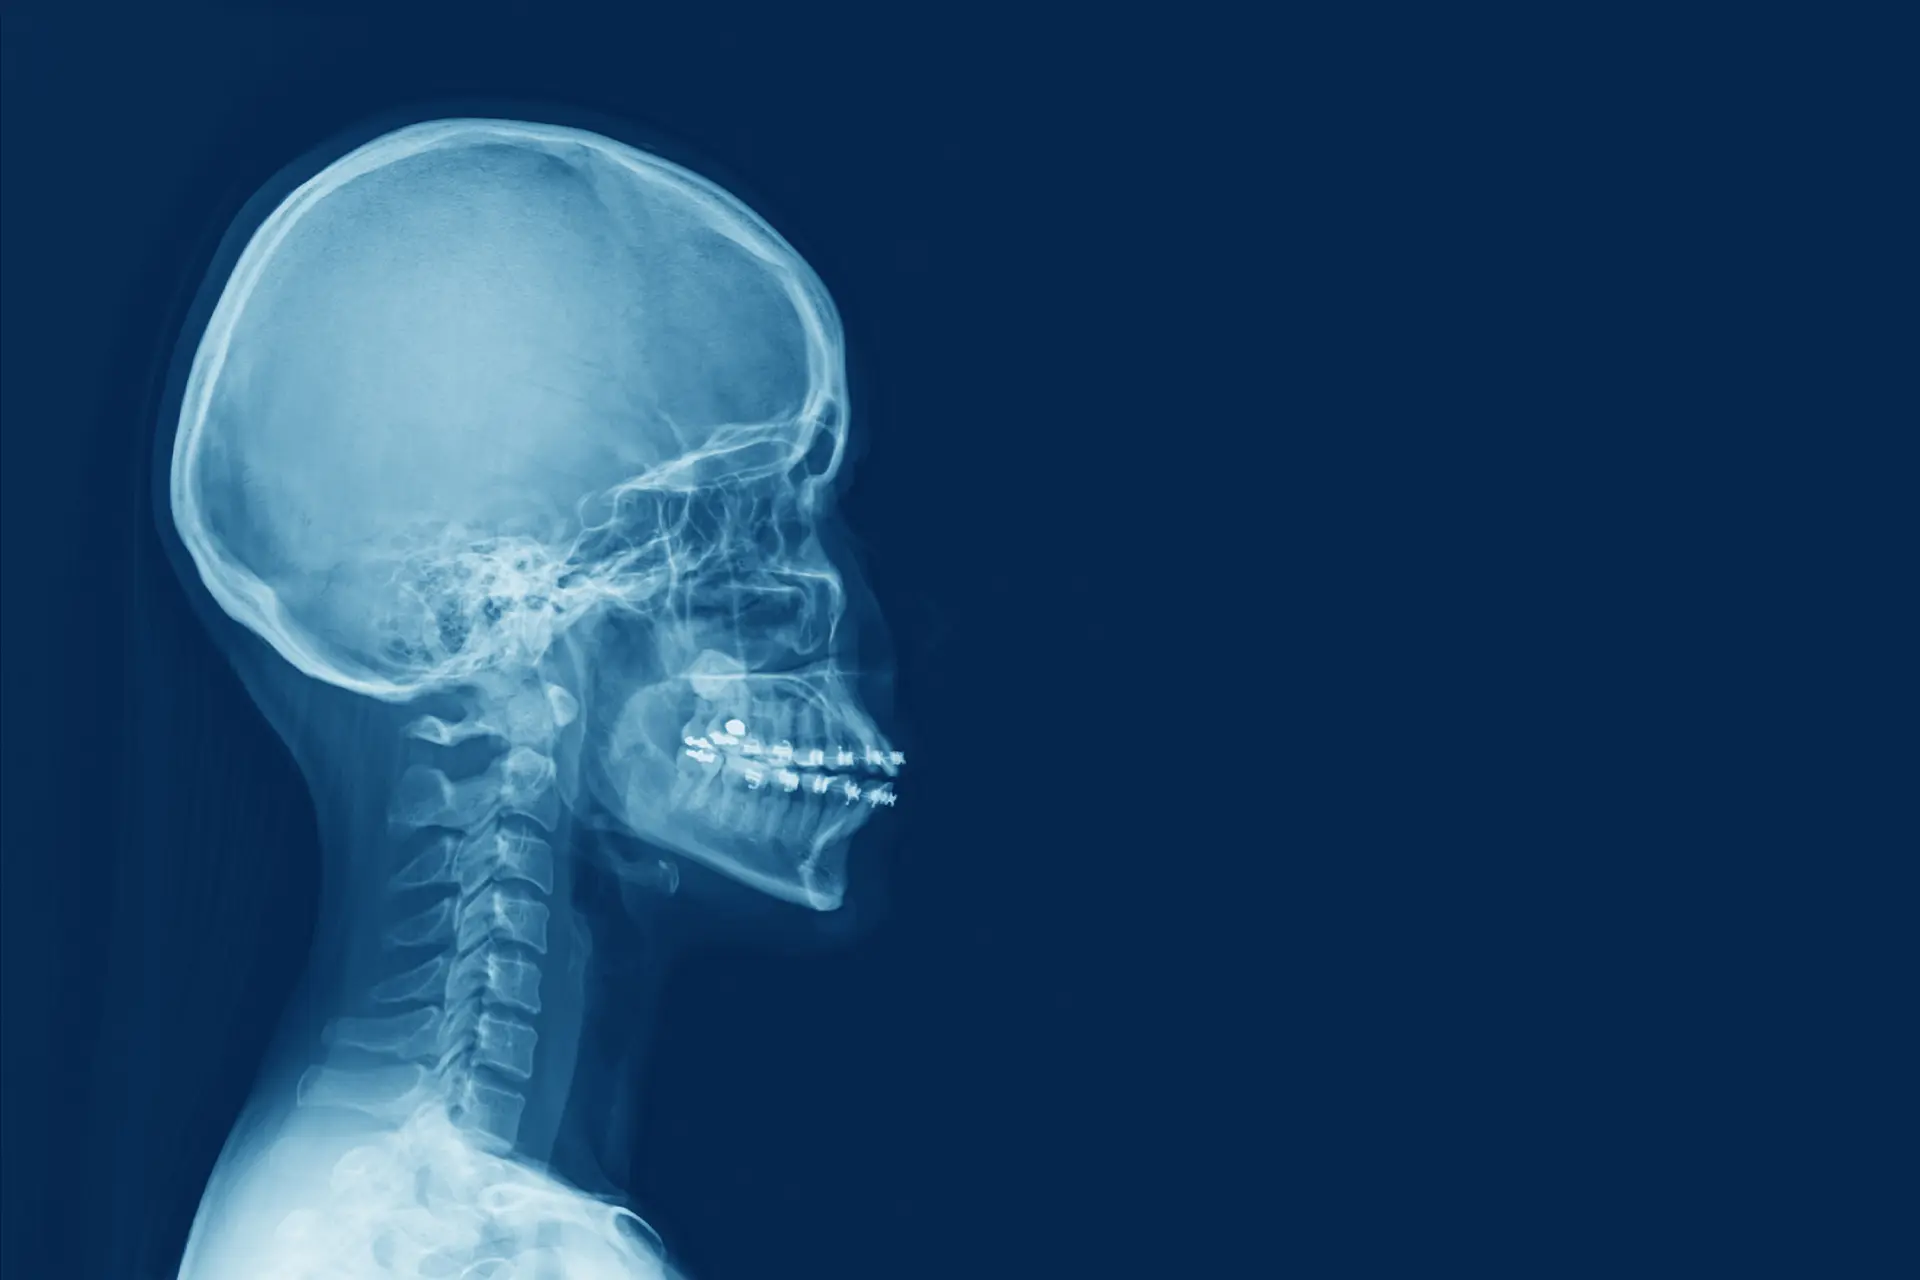

Yüz kemik kırıkları estetiği, genellikle yüz kemiği kırıklarının düzeltilmesi amacıyla gerçekleştirilen cerrahi müdahaleleri ifade eder. Bu operasyonlar, genellikle yüz kemiği kırıkları, çene kemiği kırıkları, burun kemiği kırıkları veya alın kemiği kırıkları gibi durumları düzeltmek için yapılır. Bu müdahaleler, genellikle estetik görünümü iyileştirmenin yanı sıra, yüzün fonksiyonlarını geri kazanmaya ve yaşam kalitesini artırmaya yöneliktir.

Cerrahi Müdahale

Cerrahi müdahale genellikle kırıkların yerine getirilmesini, düzeltilmesini ve sabitlenmesini içerir. Bu, cerrahın tercih ettiği tekniklere bağlı olarak değişebilir.